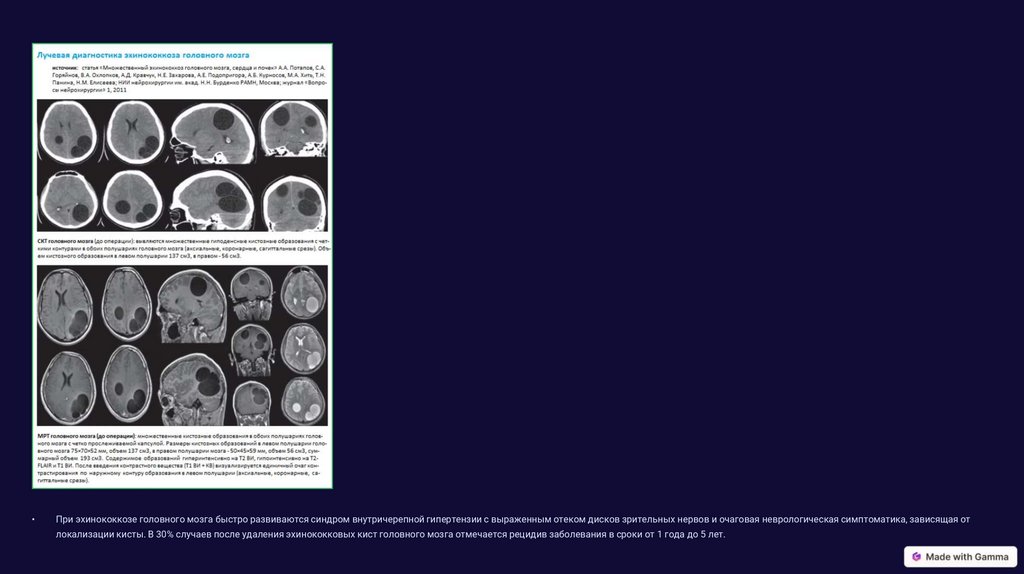

Поражение головного мозга при кистозном эхинококкозе (КЭ) составляет приблизительно 1 - 3% всех случаев заболевания, крайне редко встречается поражение спинного мозга. Эхинококковые кисты обычно имеют

шаровидную форму и характеризуются медленным ростом. Их размер составляет в среднем 4 - 10 см в Ø.

При эхинококкозе головного мозга быстро развиваются синдром внутричерепной гипертензии с выраженным отеком дисков зрительных нервов и очаговая неврологическая симптоматика, зависящая от

локализации кисты. В 30% случаев после удаления эхинококковых кист головного мозга отмечается рецидив заболевания в сроки от 1 года до 5 лет.